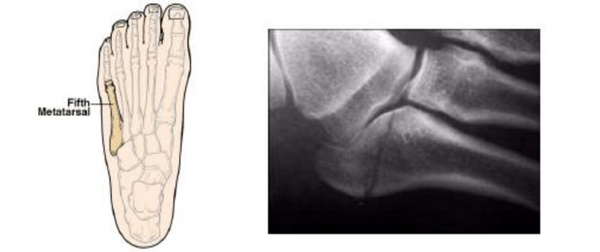

- You have fractured a bone on the outer part of your foot.